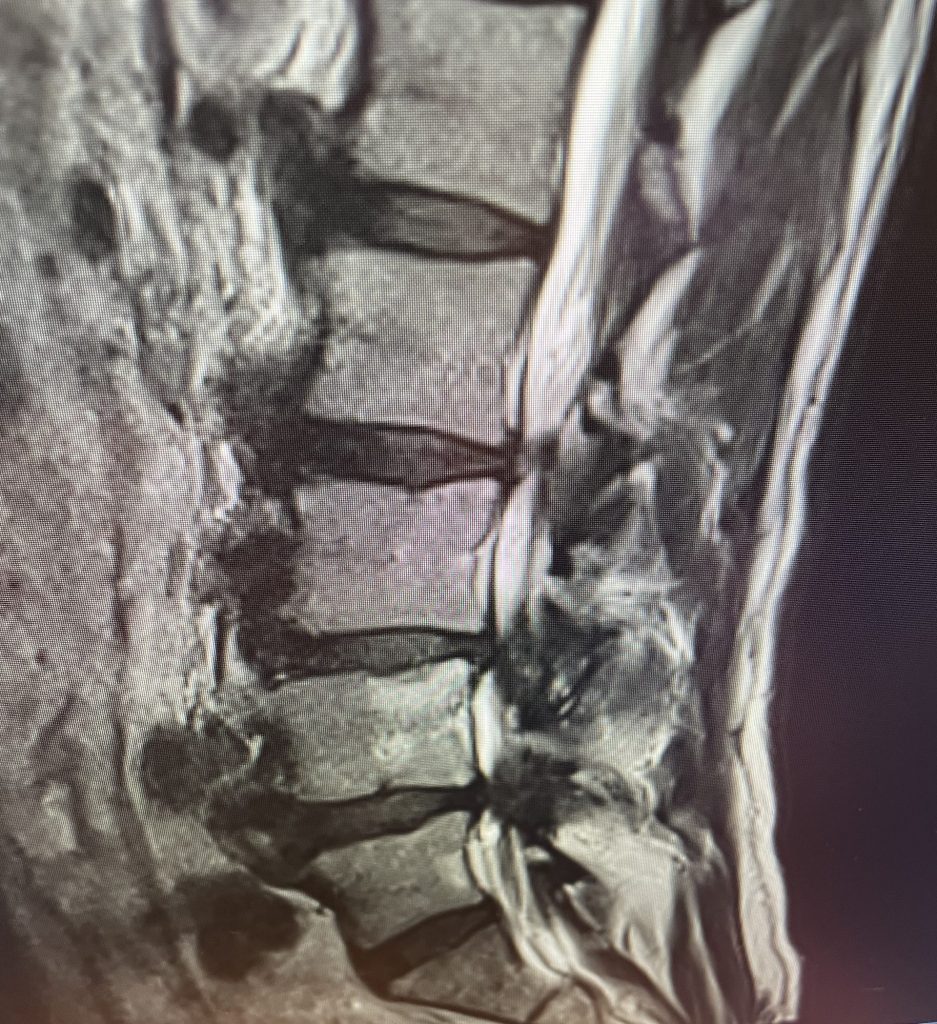

This 71 year-old male presents with a long history of progressive pain in the low back with radiation to both legs in the anterior thigh distribution, the left being worse than the right. He feels that his legs get weak. Standing and walking worsen the low back pain and lower extremity symptoms while sitting relieves the symptoms. He failed PT and epidural injections. Imaging studies revealed severe lateral recess stenosis do mainly to severed thickened ligament. He had severe lateral recess stenosis from L2-5 (Fig 4) as well as central stenosis. He also had a slight retrolisthesis at L3-4 and L4-5. He had on the left in particular a very enlarged protruded segment of thickened ligamentum in the subarticular recess at L3-4 (Fig 5) which was likely responsible for his left leg pain as the patient had symptoms of an L4-type syndrome. It was decided to perform a decompressive laminectomy from L2-5. Because of retrolisthesis it was decided to perform a noninstrumented onlay bone fusion or an in situ fusion from L3-5. In this case it was very important to decompress not only the thecal sac, but also the lateral recess with the thickened ligament at the point where the nerve makes its course into the forman. As a surgeon you must really undercut the facet joints to clear the lateral recess and feel how the nerve root with one’s instrument is being released as it enters the foramen. Postoperatively the patient had resolution of his leg pain, particularly on the left. In this case the most significant pathology was in the left L3-4 lateral recess, his symptoms and MRI findings correlated well which leads to the most successful operations.

Figure 4: Sagittal T2-weighted MRI demonstrating severe lateral recess stenosis from L2-L5 as well as slight retrolisthesis at L3-4 and L4-5.

Figure 5: Axial T2-weighted MRI demonstrating severe bilateral lateral recess stenosis secondary to thickened ligamentum flavum. Notice the prominence of the left ligamentum in the subarticular recess.